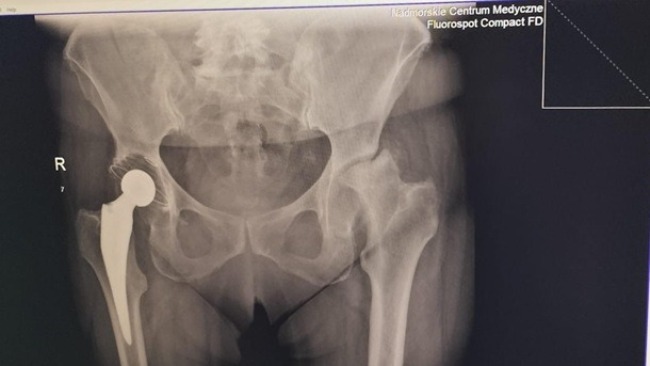

6 lat temu przeszła wymianę prawego stawu biodrowego. Niedługo po operacji znacząco pogorszył się stan jej kolan, na których operację musi czekać 5 lat.

Operacja kolan zeszła jednak na drugi plan, ponieważ w listopadzie zeszłego roku bardzo pogorszył się stan jej lewego biodra (widoczny na zdjęciu rentgenowskim).